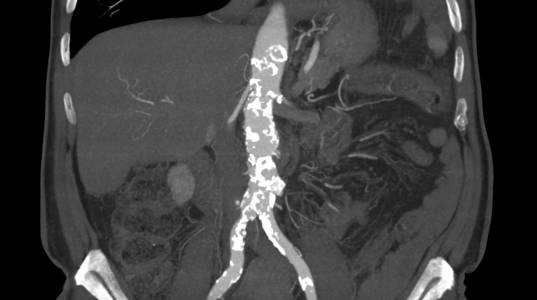

Paciente da entrada hospitalar com dor cardíaca típica sendo diagnosticado com infarto agudo do miocárdio em dezembro de 2019. Apresentava passado de outros três episódios e de revascularização cardíaca com mamária e ponte de safena. Durante internamento paciente evolui com dor abdominal importante sendo indicada realização de tomografia de abdome total que indicou a presença de hematoma intramural da aorta abdominal.

Haja vista a extensa quantidade de comorbidades a cirurgia aberta se fazia de risco muito elevado para o paciente. Este foi então encaminhado para correção endovascular.

O estudo de angiotomografia evidenciou que as artérias iliacas externas e femorais apresentavam-se com muitas calcificações e ponto de estenose mais crítica em artéria ilíaca comum direita. Diante dos achados de imagem, foi optado por endoprotese de aorta abdominal de baixo perfil (Incraft – Cordis).